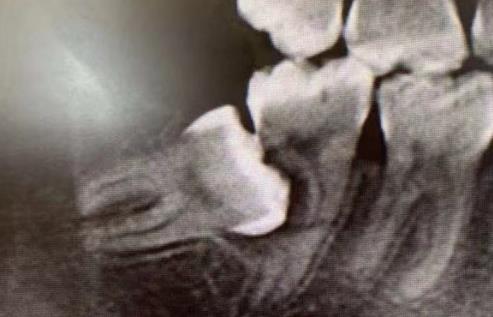

如果鄰牙齲壞很嚴(yan) 重沒法保留了,但是智齒是健康完整的,而且**有做牙齒矯正的需求,可以考慮及時拔除鄰牙,拔智齒牽引出來頂替鄰牙使用。

第二磨牙缺失後,正畸成功牽引了智齒